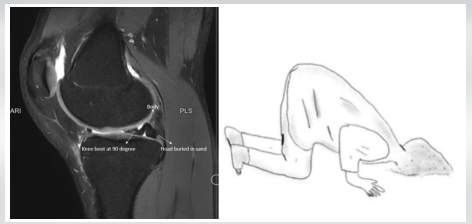

Bucket Handle Tear of the Medial Meniscus with a New Magnetic Resonance Imaging Sign: The “Head in the Sand Sign” – A Case Report

Joseph Sajeev , Anand Raj Rajendrababu , Jerin Jeevo , Velpula Mohan Babu , Raphael Thomas , Rajkumar S Amaravati

………………………………p.9-13